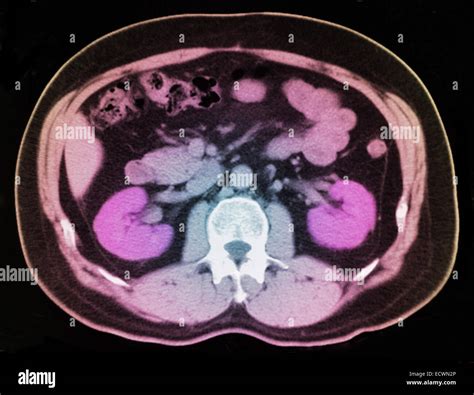

Non-Contrast Computed Tomography (CT) Scan

The non-contrast CT scan of the abdomen and pelvis is considered the gold standard for detecting kidney stones. It is highly sensitive, meaning it is excellent at finding even very small stones that other tests might miss. Because it does not require intravenous contrast dye, it is relatively quick and safe for most patients, including those with kidney function issues.